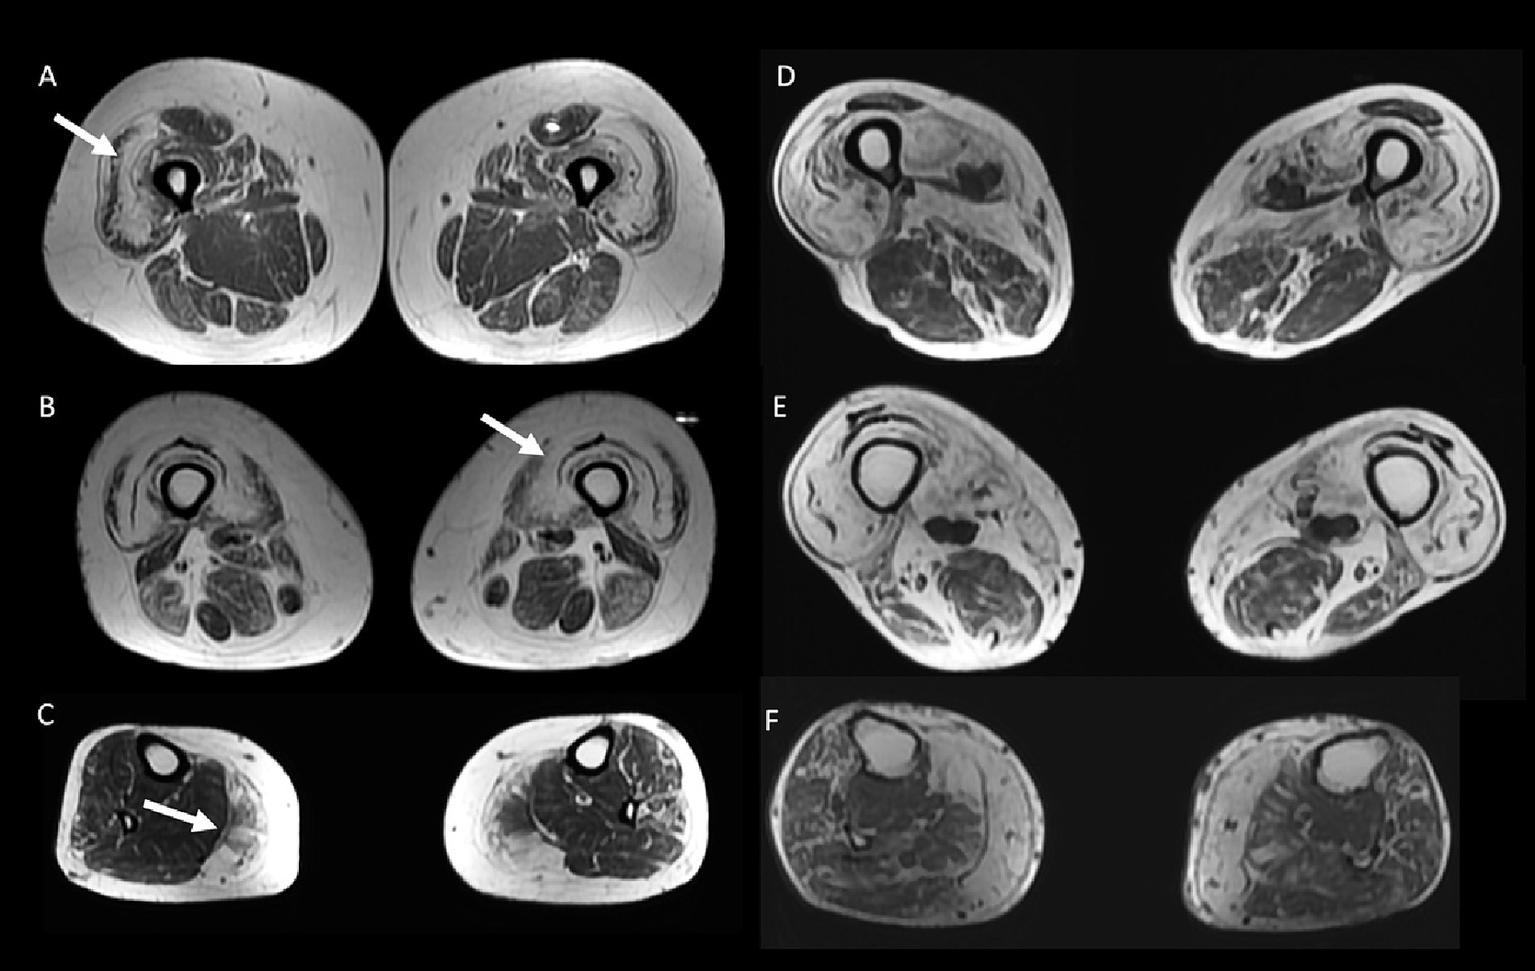

50 year-old female with inflammatory myopathy with mitochondrial pathology (IM-Mito) (A–C) presents axial fast spin-echo T1-weighted Whole-Body Muscle Magnetic Resonance Imaging (WBMRI) showing moderate-severe fatty infiltration in quadriceps muscle with relatively spared rectus femoris muscle compared to other quadriceps muscles (A,B) and severe fatty infiltration in medial gastrocnemius muscle (C). Axial fast spin-echo T1-weighted WBMRI in a 78 year-old male with inclusion body myositis (D–F) shows similar imaging appearance compared to IM-Mito shown in (A–C).

Other general radiological findings are shown in Table 7. Muscle edema in at least one muscle was found in most patients with IM-Mito and IBM (Figure 5), but there was no significant difference between the two groups. The mean number of muscles with edema per patient was also similar between the two groups. Asymmetry was observed in most study participants; however, there was no statistically significant difference between patients with IM-Mito and IBM. Most participants with IM-Mito and IBM showed relatively spared rectus femoris muscle compared to other quadriceps muscles (Figure 4). Nevertheless, no statistically relevant difference was found between the groups. The most compromised upper limb muscle by edema or fatty infiltration in patients with IM-Mito and IBM was the flexor digitorum profundus (Figure 6). Although not statistically significant, there was a trend towards greater radiological involvement of these muscles in individuals with IBM compared to those with IM-Mito (100% vs. 64.3%, respectively, p = 0.05).

| Rectus femoris relatively spared compared to other quadriceps muscles | 13 (92.9%) | 8 (80.0%) | 0.550 |